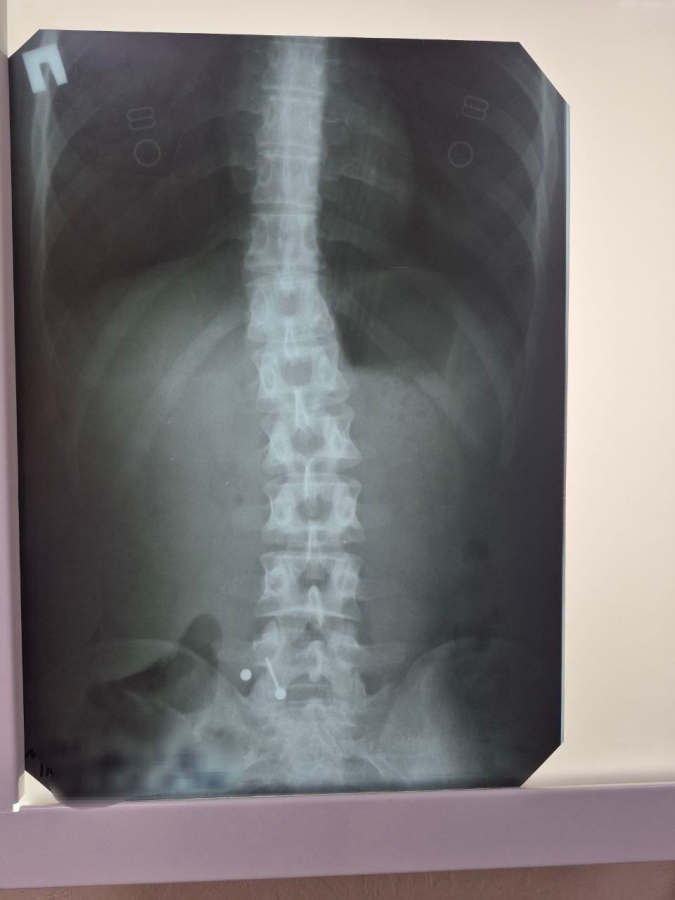

Девушка обратилась в стационар не сразу, а когда раскрутившиеся металлические части (шарик и штанга) уже покинули желудок и переместились в тонкий кишечник. Это сделало эндоскопическое извлечение без рисков осложнений невозможным.

Во втором случае в стационар попал двухлетний малыш, который, со слов мамы, примерно за час до обращения проглотил саморез. При каких условиях произошел инцидент, выяснить не удалось. Рентген подтвердил наличие острого металлического предмета внутри ребенка.

Саморез, к счастью, расположился шляпкой вниз, а острой частью вверх, что позволило предотвратить повреждение стенок желудочно-кишечного тракта и слизистой желудка. Благодаря этому удалось избежать необходимости проведения сложного открытого оперативного вмешательства. Мама ребенка отказалась от дальнейшей госпитализации, а малыш выписан под амбулаторное наблюдение. Саморез теперь войдет в коллекцию эндоскопистов больницы, в которой уже десятки самых необычных предметов.